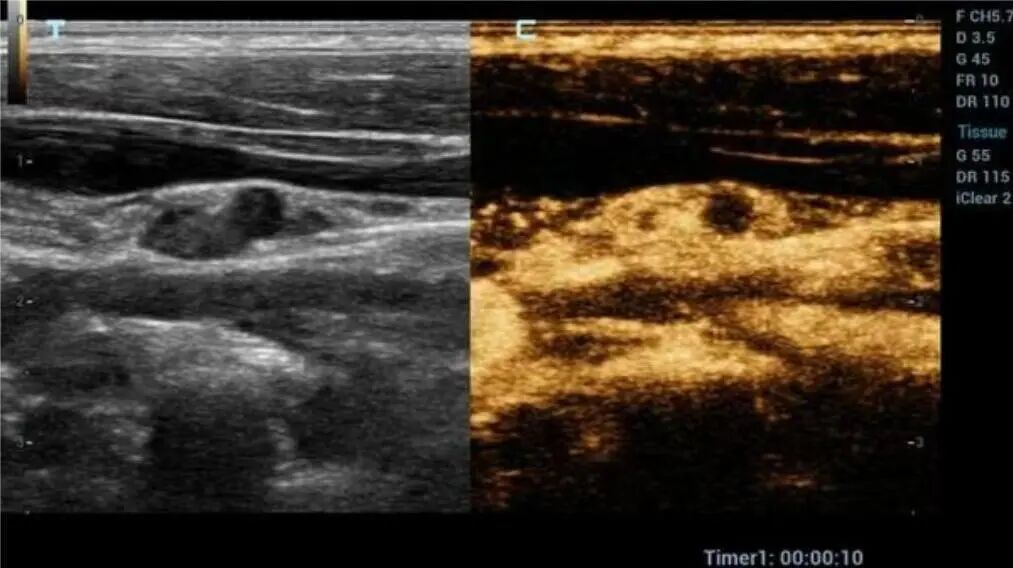

1月7日,贵州航天医院第91次晨读会由我院超声科医师杨向蓉作学术交流,她以“小微泡,大作用——右心声学造影”为题,详细讲解了右心声学造影的基本原理、适用情况、操作方式及心脏异常分流评估特点等内容,涵盖了该技术的实施条件、所用造影剂类型及多种激发试验方法,并通过多个病例图文资料分享了右心声学造影在相关症状病因探寻中的辅助角色,为临床评估提供了一种观察途径,有助于从循环角度了解某些症状的可能原因,在相应症状的病因分析中具有一定的参考意义。 贵州航天医院 超声科专家简介 吴艳辉 中共党员,超声科学科带头人,主任医师 专业擅长:从事超声诊断工作30余年,对心血管、小器官超声、超声引导下介入等具有丰富的临床经验。 胡大海 超声科主任,副主任医师 专业擅长:从事超声工作20余年,对心血管、外周血管、浅表器官、成人颅脑、超声造影诊断及超声引导下介入等具有丰富的临床经验。 骆科美 中共党员,超声科副主任医师 专业擅长:从事超声诊断工作30余年,对胎儿心脏及颅脑、妇产超声诊断、盆底超声等具有丰富的临床经验。 刘 敏 超声科副主任医师 专业擅长:从事超声诊断工作20余年,对妇产科超声、心脏血管超声诊断具有丰富的临床经验。 韩锡铁 超声科副主任医师 专业擅长:从事超声诊断近20年,对心血管、外周血管、浅表器官、肌骨神经超声诊断具有丰富的临床经验。 杨向蓉 中共党员,超声科主治医师 专业擅长:从事超声诊断工作16年,擅长心血管、浅表器官、盆底、腹直肌超声、右心声学造影及超声引导介入等技术。 贵州航天医院超声科简介 基本情况 贵州航天医院超声科配备多种超声检查设备(飞利浦彩超(IU-22、IU-Elite、EPIQ5、EPIQ7),迈瑞彩色超声(ResonaI9T、RechoR9、Resona I9、DC-8)、GE-VolusonE8、汕头SIUIAPogee6800、床旁彩色超声诊断仪等),设有心血管诊室、外周血管诊室、妇产科诊室、腹部诊室、绿色通道、浅表小器官等检查室。 诊疗范围 科室业务覆盖腹部、泌尿、妇科、产科(常规、NT筛查、系统筛查及高危妊娠监护)、成人心脏、外周血管、浅表器官(包含甲状腺、乳腺、阴囊、眼睛等)、颅脑(小儿颅脑、成人帕金森辅助筛查)、小儿肺超、超声造影、盆底、腹直肌、肌骨神经等检查及各种超声介入引导。 专科特色 四肢血管超声检查、产前系统筛查及超声监护、超声造影检查技术、介入超声临床应用、经颅脑实质超声辅助筛查诊断帕金森病、小儿髋关节筛查、女性性早熟超声诊断、盆底、腹直肌超声检查等。 NT超声检查 超声介入引导 肝脏超声造影 甲状腺造影 颅脑超声帕金森辅助检查 乳腺超声造影 上肢动静脉造瘘超声检查 双胎超声筛查 下肢血管超声检查 右心造影 end